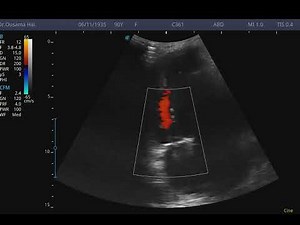

Diagnosing Aortic Stenosis | Heart Valve Failure